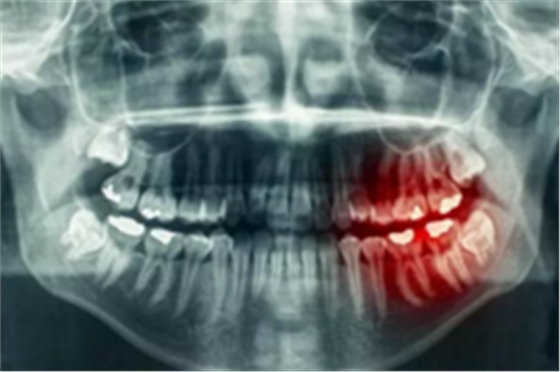

牙齒長(zhǎng)在牙槽骨里,形態(tài)變化多端,所需要的手術(shù)時(shí)間及手術(shù)風(fēng)險(xiǎn)也有差別,所以醫(yī)生會(huì)要求拔牙前給你進(jìn)行X線牙片檢查,遇到疑難病例還要進(jìn)行牙科三維CT檢查。

為什么有些牙齒不能拔?拔牙無小事!

這些檢查手段可以讓醫(yī)生知道你牙根的長(zhǎng)短、大小、數(shù)量、走向、彎曲程度、與周圍重要結(jié)構(gòu)的關(guān)系等等。只有明確拔牙方法,并評(píng)估拔牙風(fēng)險(xiǎn),才能使你這顆牙拔得更順暢。